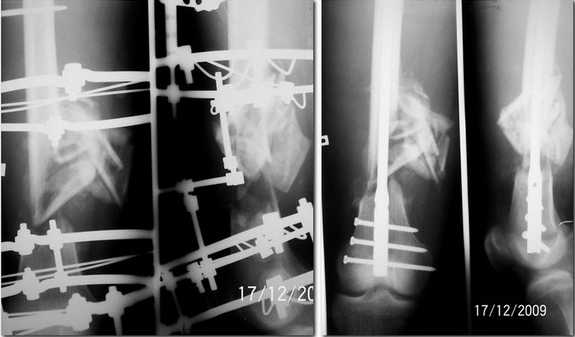

Николов Олег 18 Декабрь 2009, 01:41

Прислушавшись к мнению уважаемых коллег провели двухэтапное лечение пациента. Пару дней

назад забили штифт, без укорочения, колено редрессировали до 90гр. Всем спасибо за дельные

советы.

Отправитель: Ерсин Жунусов 19 Декабрь 2009, 02:12

Уважаемые коллеги! Очень демонстративный и профессионально проведенный остеосинтез. Удачи, так держать! С уважением Ерсин Жунусов.

Отправитель: Alexander Chelnokov 19 Декабрь 2009, 03:20

Поздравляю, очень симпатично получилось.